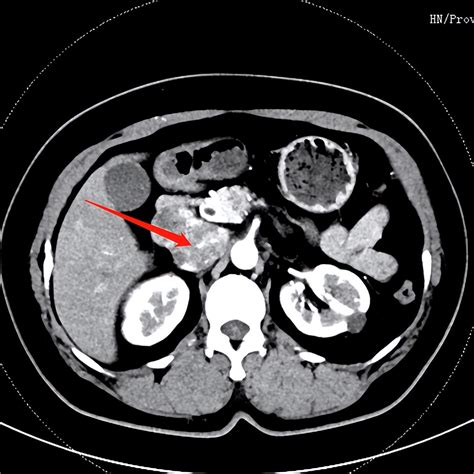

• Computed Tomography (CT) Scan: A detailed imaging technique that provides cross-sectional images of the IVC and surrounding structures. It is useful for detecting aneurysms, thrombi, and other pathologies.